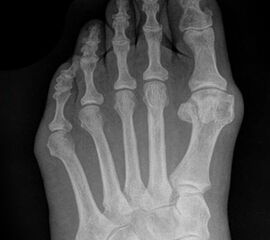

Abb. 9 a, b: Typ III Deformität mit prä- (a) und postoperativem Röntgenbild (b).